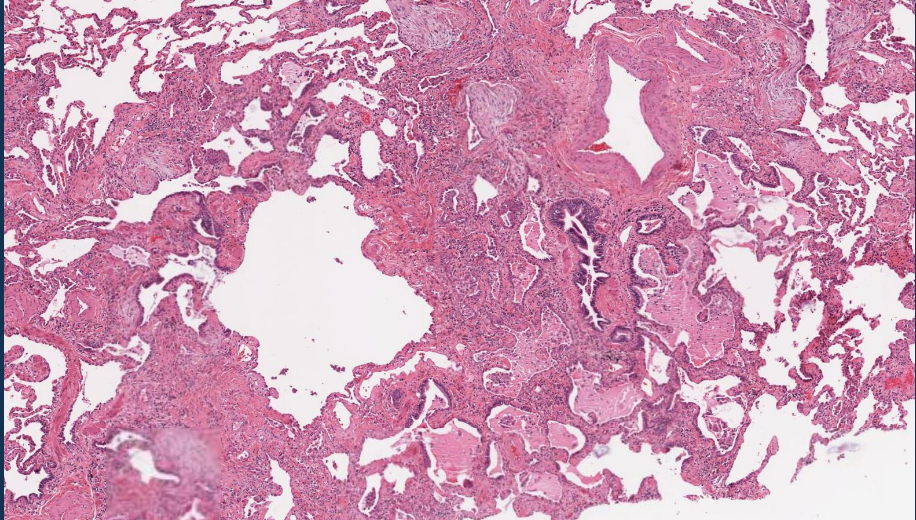

Enfermedades relacionadas con el asbesto:

Placas fibrosas localizadas

Derrame pleurales

Fibrosis intersticial parenquimatosa (asbestosis)

Cuáles son las dos formas geométricas

Serpentina 90%

Anfíbol, más patógeno

Una vez fagocitadas por los macrófagos, las fibras de asbesto o amianto activan el … y estimulan la liberación de factores proinflamatorios y mediadores fibrogénicos

inflamasoma

Dónde ocurre la lesión inicial de asbesto

En las bifurcaciones de las vías respiratorias pequeñas

¿Por qué se le denomina cuerpo ferruginoso?

Las fibras de amianto quedan recubiertas de hierro y calcio

¿Cómo se distingue la fibrosis intersticial difusa causada por asbesto de que de otras?

Cuerpos de amianto

¿Qué son los cuerpos de amianto?

Varillas de color marrón dorado, fusiformes con un centro translúcido

Enfermedades relacionadas con el asbesto MORFOLOGÍA

solo ver